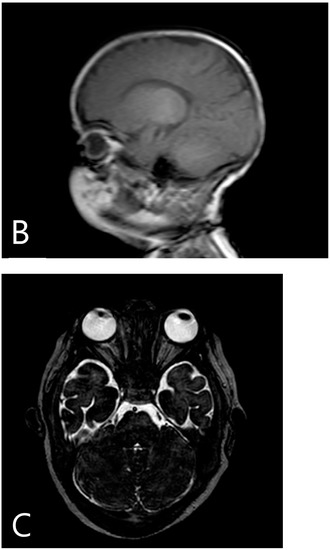

A six-month-old male patient diagnosed with ARO was admitted to our transplantation unit. The patient’s clinical presentation was characteristic of the disease: deformed sclerotic skull, multiple fractures, optic nerve atrophy with progressive visual impairment, and thrombocytopaenia with hepatosplenomegaly as the sign of bone marrow involvement. The auditory system is often affected in ARO, but the patient showed no sign for otologic involvement of the disease at this time. Diagnostic radiography of the chest and cranial MRI can be seen in Figure 1.

Figure 1.

Pre-transplantation radiography (A) shows increased bone density, rachitic malformation in ribs, and endobone appearance in vertebrae and humeri. Sagittal T1-weighted MR image (B) demonstrates the sclerosis of the calvaria. Axial T2-weighted MR image (C) shows optic canal stenosis and optic nerve atrophy.